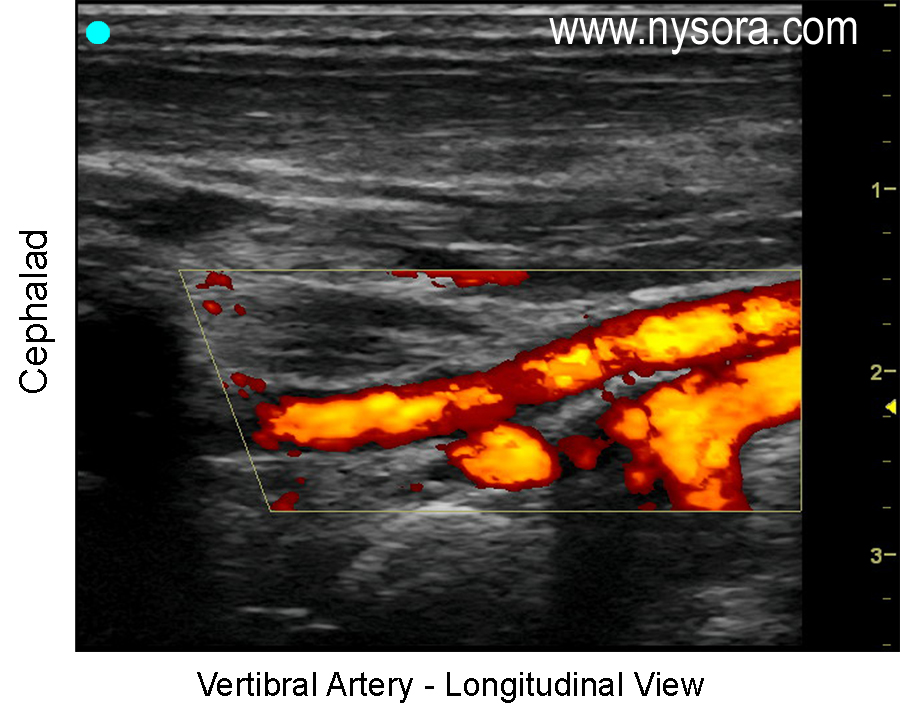

Ultrasound image of the vertebral artery longitudinal view